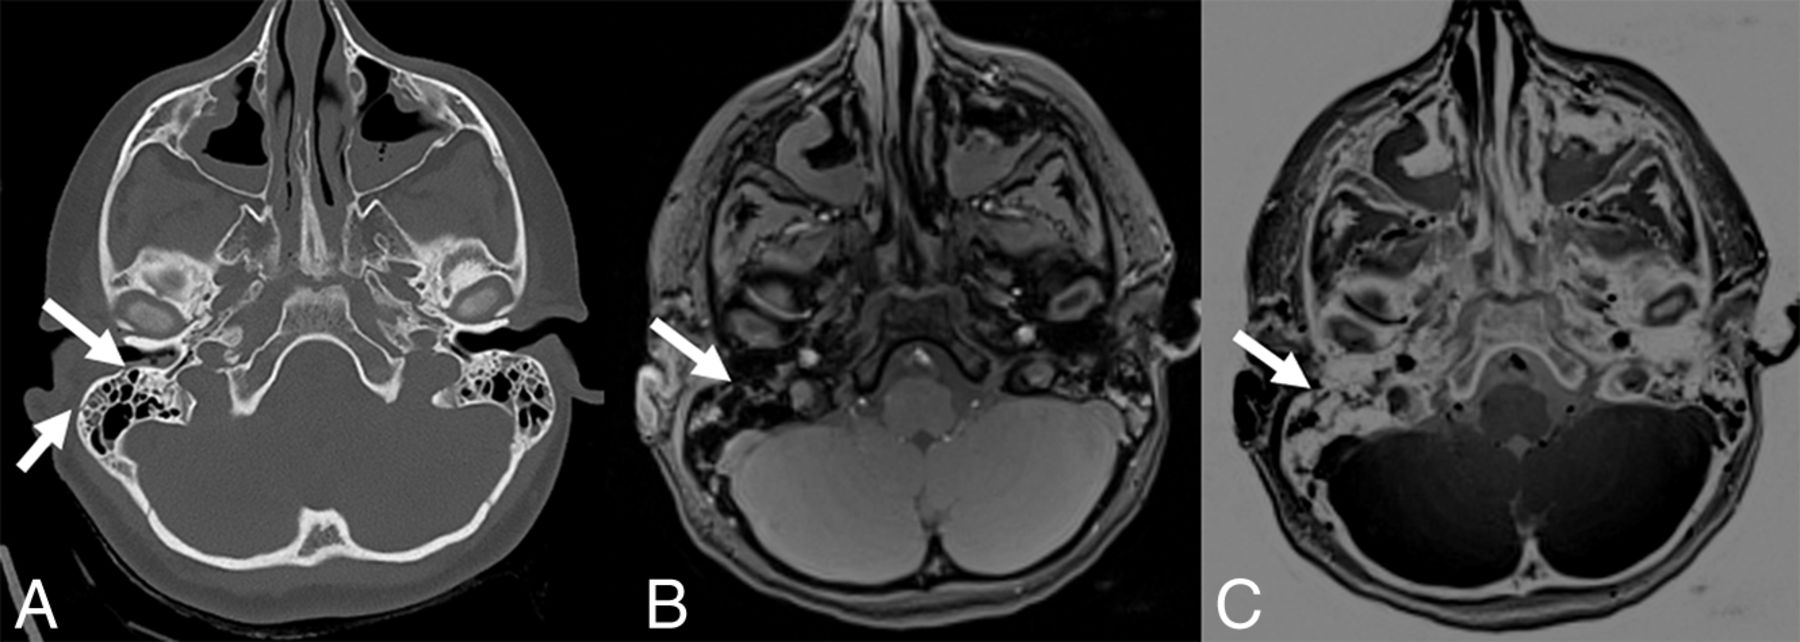

The third false-negative case was an older child in whom a linear fracture was misinterpreted as a venous transosseous vascular channel. More familiarity with the black bone sequence and the use of 3D reconstruction could potentially help overcome this problem. The fourth case of a missed linear fracture on black bone MR imaging was a fracture in the mastoid region (Fig 2). This case highlights the main limitation of black bone MR imaging: In anatomic regions where bone abuts air (mastoid, craniofacial sinuses), the distinction between air and bone is difficult because both have low signal intensity on this sequence.10 The application of black bone MR imaging at air-bone interfaces is challenging and requires experience with the technique and careful review of the images.

A, Axial CT image shows 2 small nondisplaced linear fractures of the mastoid (arrows). On black bone (B) and inverted black bone (C) MR images, these fractures are barely visible (arrows).